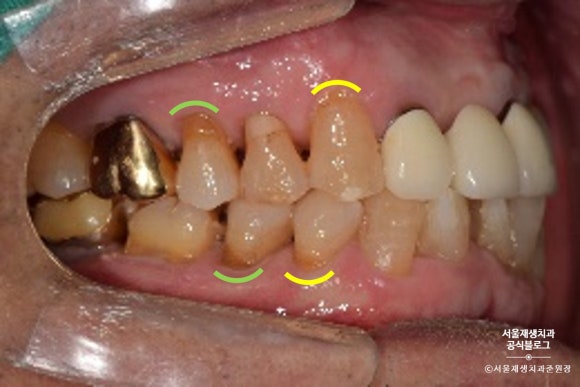

노란색으로 표시된 치아들은 상대적으로 전방에 위치하여 레진으로 치료하기로 했습니다.

연두색으로 표시된 치아들은 상대적으로 후방에 위치하여, 심미성이 조금 떨어지더라도 비용이 저렴한 글라스아이오노머로 치료하기로 했습니다.

※■■레진으로 치료 예정

※■■ 글라스아이오노머(GI)로 치료 예정